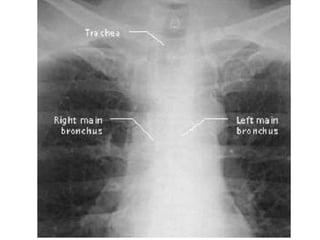

CXR